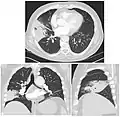

On a posteroanterior and lateral chest radiograph, an entire lobe will be radiopaque, which is indicative of lobar pneumonia.[5]

Chest radiograph of a lobar pneumonia, affecting the right middle lobe.

CT scan of the same case.